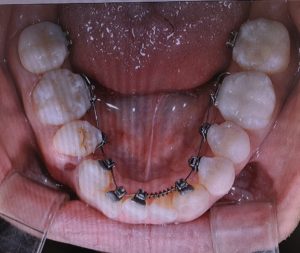

【上あご】

<フルリンガル装着時 2018/08/31>

<1回目調整後 2018/10/05>

<矯正インプラント装着時 2018/11/03>

※わずかずつですが、前歯のアーチが形成されつつあります。